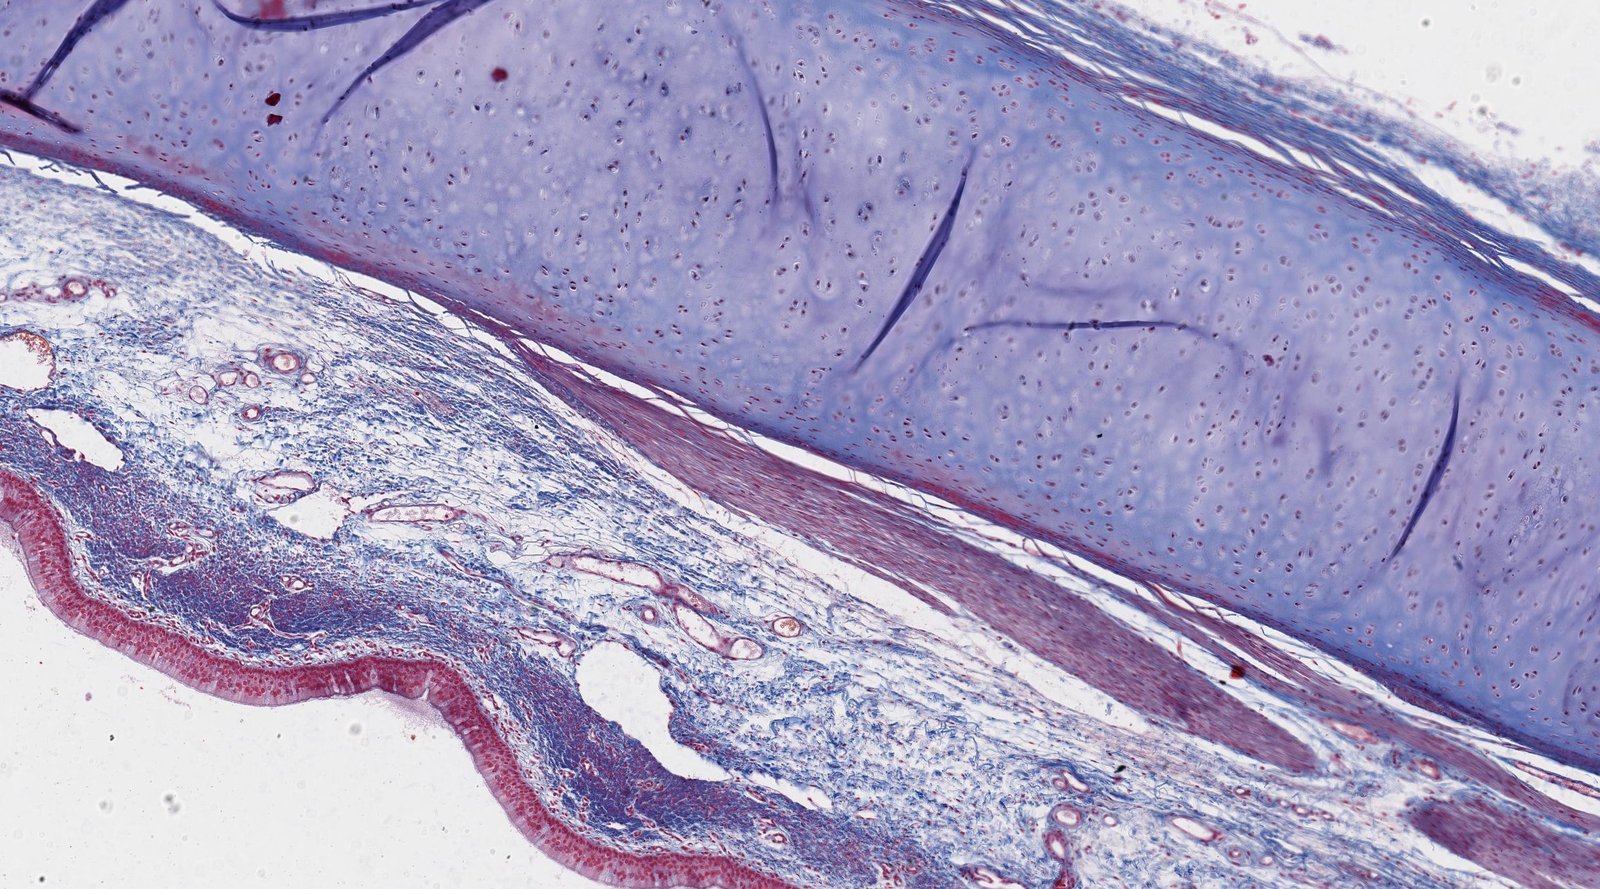

• Trachea and bronchi

• Pseudostratified ciliated columnar epithelium: important for mucociliary clearance

• Goblet cells

• Cartilage: C-shapedhyaline cartilage rings in the trachea and hyaline cartilage plates in the bronchi provide structural support.

• Annular ligaments of trachea: horizontal fibrous bands that join the tracheal cartilage rings together

• Smooth muscle

• Seromucous glands (secrete mucus)

• Basal cells